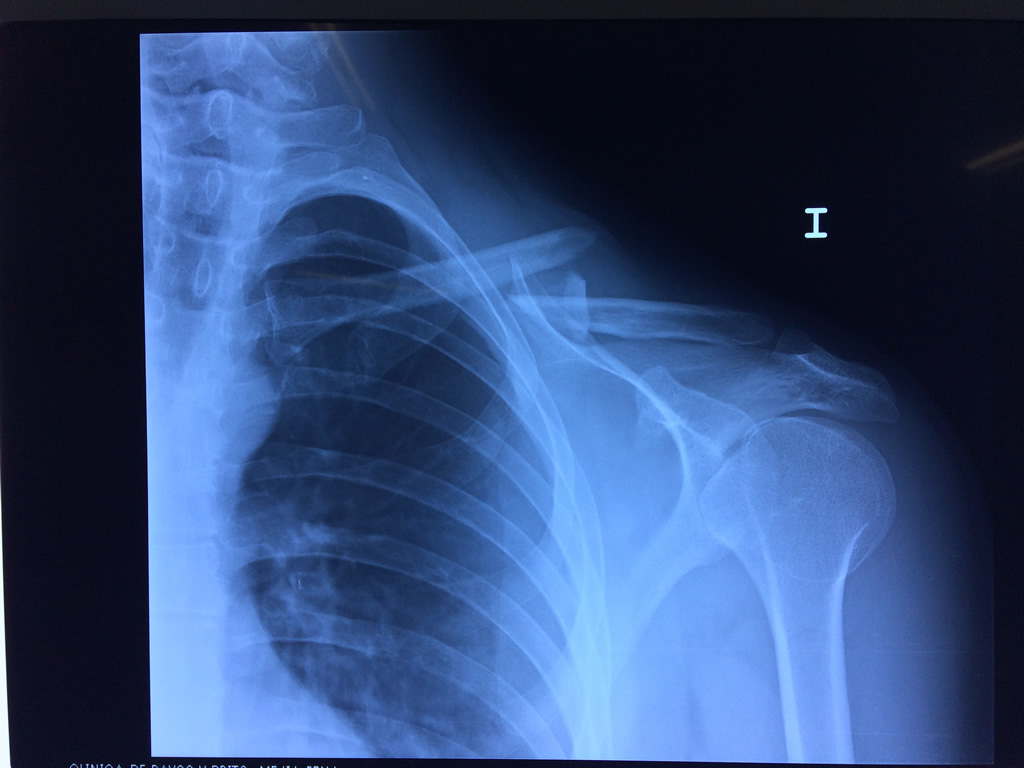

Cirugias en El Salvador - Clavícula